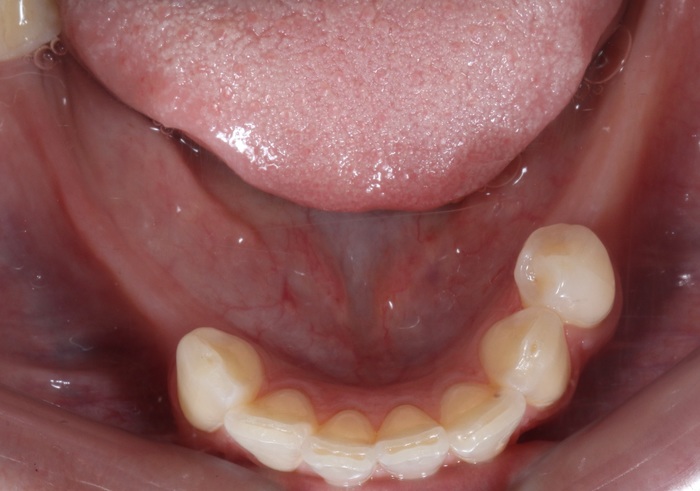

Коронки на имплантатах на нижней челюсти:

Параллельно я удалил два центральных верхних резца, после чего были зафиксированы все остальные временные коронки.

Подчеркну - коронки временные (!), все они будут заменены на постоянные.

Будут одинакового цвета и тд и тп.